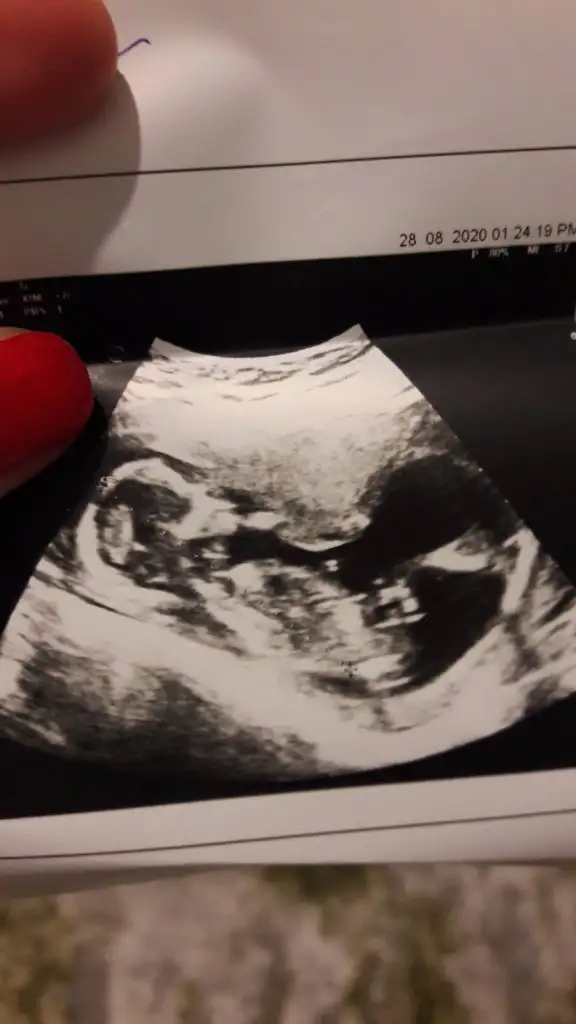

• 20200828_193424.webp

20200828_193424.webp

18,1 KB · Görüntüleme: 57

Ikra meyra Ikra meyra benim görüntü belirsiz mi acaba canim bisey demedin de görmemişte olabilirsin fikrini cok merak ediyorum.